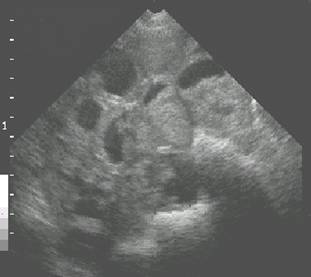

Fetal skeleton